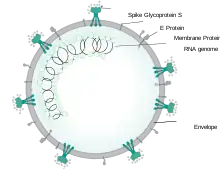

Scientifically accurate atomic model of the external structure of SARS-CoV-2. Each "ball" is an atom. |

Cause

SARS‑CoV‑2 belongs to the broad family of viruses known as coronaviruses.[107] It is a positive-sense single-stranded RNA (+ssRNA) virus, with a single linear RNA segment. Coronaviruses infect humans, other mammals, including livestock and companion animals, and avian species.[108]

Human coronaviruses are capable of causing illnesses ranging from the common cold to more severe diseases such as Middle East respiratory syndrome (MERS, fatality rate ≈34%). SARS-CoV-2 is the seventh known coronavirus to infect people, after 229E, NL63, OC43, HKU1, MERS-CoV, and the original SARS-CoV.[109]